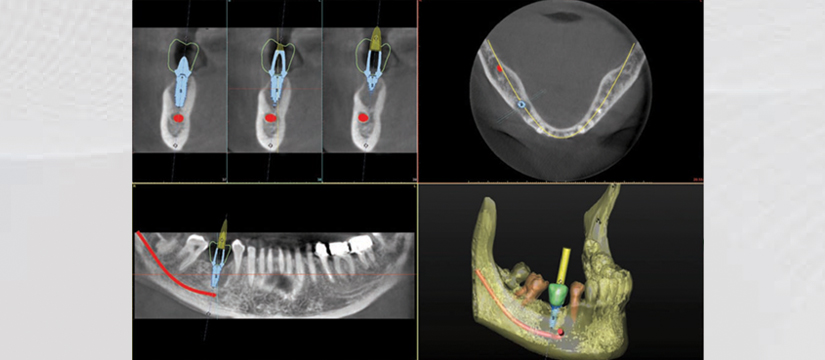

Klinika jonë premton se do t’ju ofrojë gjithnjë cilësinë më të lartë të shërbimit, me fjalën më të fundit të teknologjisë. Së fundmi ne jemi pajisur me pajisjen OWANDY IMAX TOUCH 3D. Kjo pajisje siguron me thjeshtësi dhe efikasitet imazhe high-definition për një diagnostikim të pagabueshëm. OWANDY është lideri i prodhimit të pajisjeve radiografike dentare në Francë, Amerikë, Gjermani e më gjerë. Produkti më i ri i OWANDY I-Max Touch 3D siguron të gjitha shërbimet radiografike në një aparaturë të vetme.

Aparatura posedon 17 programe të ndryshme ku mund të behën incizime si:

- 3D Dentare